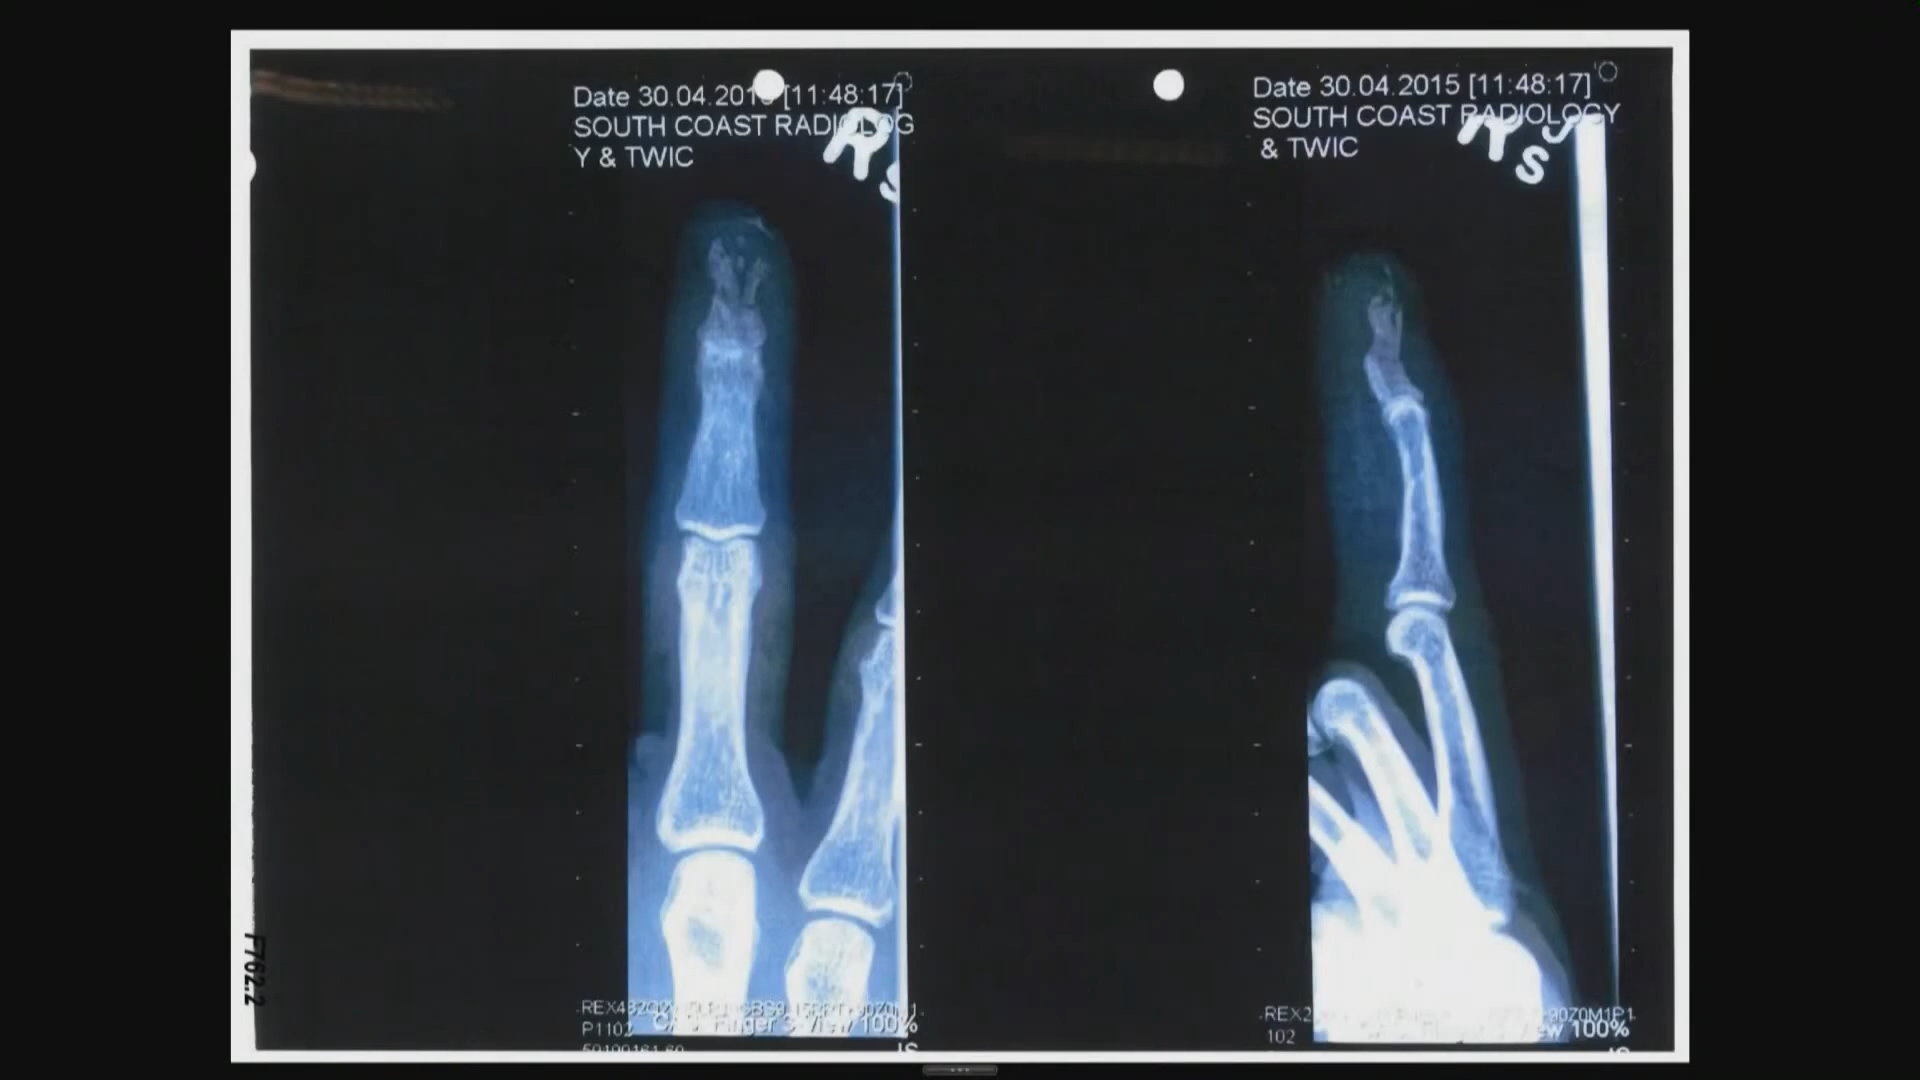

Plt144 | Finger Picture | 2015-03-08 | both parties (Days 06, 14, 20) | graphic, so link only | graphic, so link only | |

Plt145 | Finger Picture | 2015-03-09 | team JD (Days 06, 14) | |||

Def369 | Photos - finger | 2015-03 | team AH (Day 20) | according to Mr. Rottenborn already in evidence, can't find when it was used before, but if so, it was not uploaded | the published photos are pages 12 and 26 of the exhibit | |

Plt45 | 3/8/15 Gold Coast Hospital Record | 2015-03-08 | --- | --- | --- | Partial duplicate - contained in Def360 ------- BN presumably DEPP11506 |

Def359 | Email and finger photos - Kipper to Deuters, 3/8/15 | 2015-03-08 | --- | --- | --- | |

Def370 | Email - Raja Sawhany notes re finger injury, 3/8/15 | 2015-03-08 | team AH (Day 03) | not published to the jury, not in evidence due to objection | --- | |